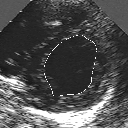

In this work, we present a new method to shape-based segmentation of deformable anatomical structures in medical images and validate this approach by detecting and tracking the endocardial border in an echographic image sequence. To this end, a global prior knowledge of the endocardial contour is captured by a prototype template with a set of admissible deformations to take into account its inherent natural variability over time. In this approach, the data likelihood model rely on an accurate statistical modeling of the grey level distribution of each class present in the image. The parameters of this distribution mixture are given by a preliminary estimation step which takes into account the distribution shape of each class. Then the tracking problem is stated in a Bayesian framework where it ends up as an optimization problem. This one is then efficiently solved by a genetic algorithm combined with a steepest ascent procedure. This technique has been successfully applied on synthetic images and on a real echocardiographic image sequence. This method seems to be particularly well suited to handle ultrasound images with strong speckle noise on which edge information cannot be exploited. Finally, the local and global minimization procedure we propose is fast, robust and do not require initialization of the template close to the desired solution. Initialization may be defined at random, leading to segmentation and tracking procedure that are completely data driven. (slides)

Figure 1:   Tracking of the endocardial contour in a medical echographic sequence at different time frames during the cardiac cycle. From top left to bottom right : frame 1, 4, 6, 9, 12, 13, 18, 20, 27, 30, 35, 40, 41, 44, 46.